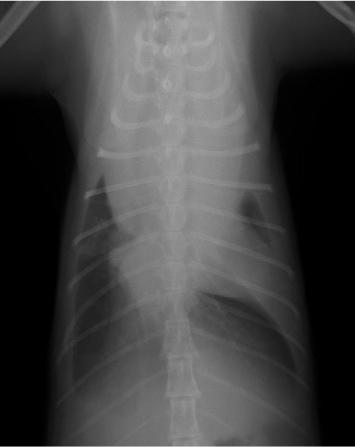

ケース:11歳10ヶ月、去勢済みの男の子、ネコちゃん

昨夜から排尿がなく、嘔吐があるとのことで来院されました。一般身体検査では、膀胱内に貯尿はなく、血液検査では腎臓の数値が著しく上昇していました。急性腎不全を疑い、入院治療となりました。まず、尿道内カテーテルを挿入し輸液療法と利尿剤投与を行いましたが、排尿は見られず、腎臓の数値も悪化していきました。おしっこが出ないので、体はむくみ、尿毒症による口内炎のため、よだれが出ている状態でした。ご家族とご相談の上、麻酔のリスクはありますが、腹腔内チューブを設置し、腹膜透析を行うことにしました。また、麻酔中に食道チューブの設置も行いました。腹膜透析は腹腔内チューブを介してお腹の中に透析液を注入し、2時間毎に回収しては新しい透析液を注入します。開始2日目に少量の排尿が見られるようになり、その後徐々に尿の生産が増えていき、腎臓の数値も低下していきました。透析開始6日目には腎臓の数値も低下し、排尿も見られるようになったため、腹腔チューブを抜去しました。その後も輸液療法を続けたところ、大量の排尿が見られたため、入院16日目に退院することが出来ました。退院後、しばらくは口内炎等で自力ではご飯が食べれないため、腎臓病用の流動食を食道チューブから入れていただいていましたが、退院3週間後には、口から元通り食べられるようになったため、食道チューブも抜去しました。

麻酔下で腹腔内に透析用のチューブを挿入しています。 |

透析用チューブが入ったところです。チューブは2本入れてあります。 |